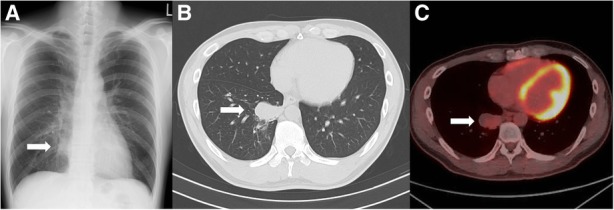

Fig. 2.

Images of the lung mass. a Chest X-ray on the first visit to our hospital. A mass lesion was shown in the right lower field (arrow), b Chest computed tomography on the first visit to our hospital. A single mass lesion (4 cm in size) was shown in the right lower lobe of the lung (arrow), c Fluorodeoxyglucose-positron emission tomography (FDG-PET) before the surgery, 4 months after the first visit. A single mass lesion was still remained in spite of the antibiotic treatment. It had abnormal uptake with a maximal standardized uptake value (SUV max) of 2.51 (arrow)

C-reactive protein level was elevated at 1.02 mg/dL as shown in the laboratory tests (Table 1). The rapid plasma reagin (RPR) and Treponema pallidum hemagglutination test (TPHA) revealed titers 1:64 and 1:5,120, respectively, although Human immunodeficiency virus testing was negative. Chest X-ray (Fig. 2a) and computed tomography (Fig. 2b) revealed a single mass lesion (4 cm in size) in the right lower lobe, and enlarged lymph nodes (4.5 cm in size) in the right inguinal region.

Diagnosed as secondary syphilis, amoxycillin 1500 mg per day and probenecid 1000 mg per day were orally administered for 2 weeks. Subsequently, rash, inguinal lymph nodes and serological markers were improved (Fig. 3), however, the lung mass remained unchanged in size (Fig. 2c). TBB confirmed the pulmonary involvement of syphilis by PCR techniques (tpp47-, and polA-PCR) (Fig. 4), whereas malignancy and other possible infections such as bacteria and fungi were negative (Table 2). Five months after the first visit, right basal segmentectomy was performed to exclude other comorbid diseases, especially malignancy. The remained lung mass was an abscess and histological analysis showed the granuloma formation by epithelioid histiocytes and Langhans giant cells with necrosis (Fig. 5). The comprehensive PCR tests for multi-microbes were performed in the resected lung specimens, and no microbes were significantly positive (Table 2). Subsequently, penicillin G 2.4 million units per day was intravenously administered for 2 weeks, and the pulmonary involvement has resolved without relapse after 8 months follow-up.